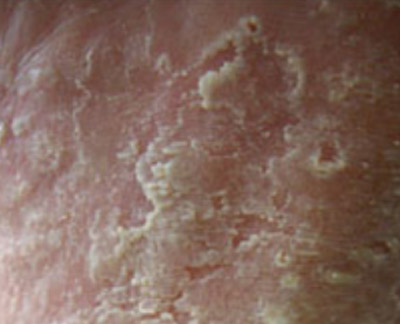

手足癣

足癣俗称脚气、香港脚,是由皮肤浅层致病真菌感染引起的,多同红色毛癣菌、石膏样毛癣菌、絮状表皮癣菌等所引起。主要有浸渍糜烂型、水疱型、鳞屑型、急性溃疡型、慢性湿疹型等。发病是有瘙痒、脱皮、化脓、疼痛难忍,且容易交叉感染,一人得病,如防护不当,易传染家人。